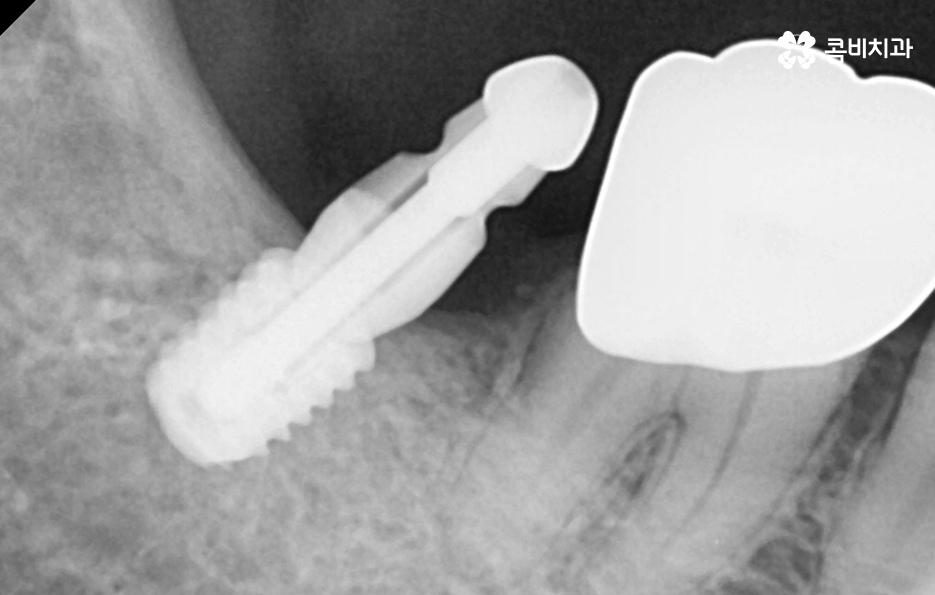

원데이임플란트는 치아 발치 후에 즉시 임플란트의 매식체 즉 인공치근으로 불리는 임플란트의 뿌리 역할을 하는 부분을 잇몸 뼈에 식립하는 치료 방법인데 사실상 임플란트의 가장 중요한 치료 단계는 단순히 임플란트를 잇몸 뼈에 식립하는 것이 아니라 잇몸 뼈에 식립된 임플란트의 인공치근이 잇몸 뼈와 골유착이 안정적으로 진행되는 과정을 거치는 것이기 때문에 골유착 과정이 약 2~3개월 정도는 보통 걸리기 때문에 하루만에 끝나는 임플란트 치료 방법은 없다고 이해하시면 좋을 거예요

우선 임플란트 치료에 있어서 뼈이식이 필요한 이유에 대해 이해하시면 좋은데 임플란트의 치료 과정에서 뼈이식을 추가적으로 진행하는 이유에는 임플란트를 식립할 잇몸 뼈의 충분한 두께와 깊이가 확보되지 않을 때 임플란트를 안정적으로 식립하기 위해 뼈이식이 진행되고 있는데요

뼈이식은 뼈가루를 말랑하게 점토처럼 반죽하여 잇몸 안에 이식을 하고 단단하게 기존의 뼈처럼 굳기 까지 평균적으로 약 2~4개월 정도가 걸리는데 환자분의 건강 상태에 따라서는 6개월 이상도 걸릴 수 있어요